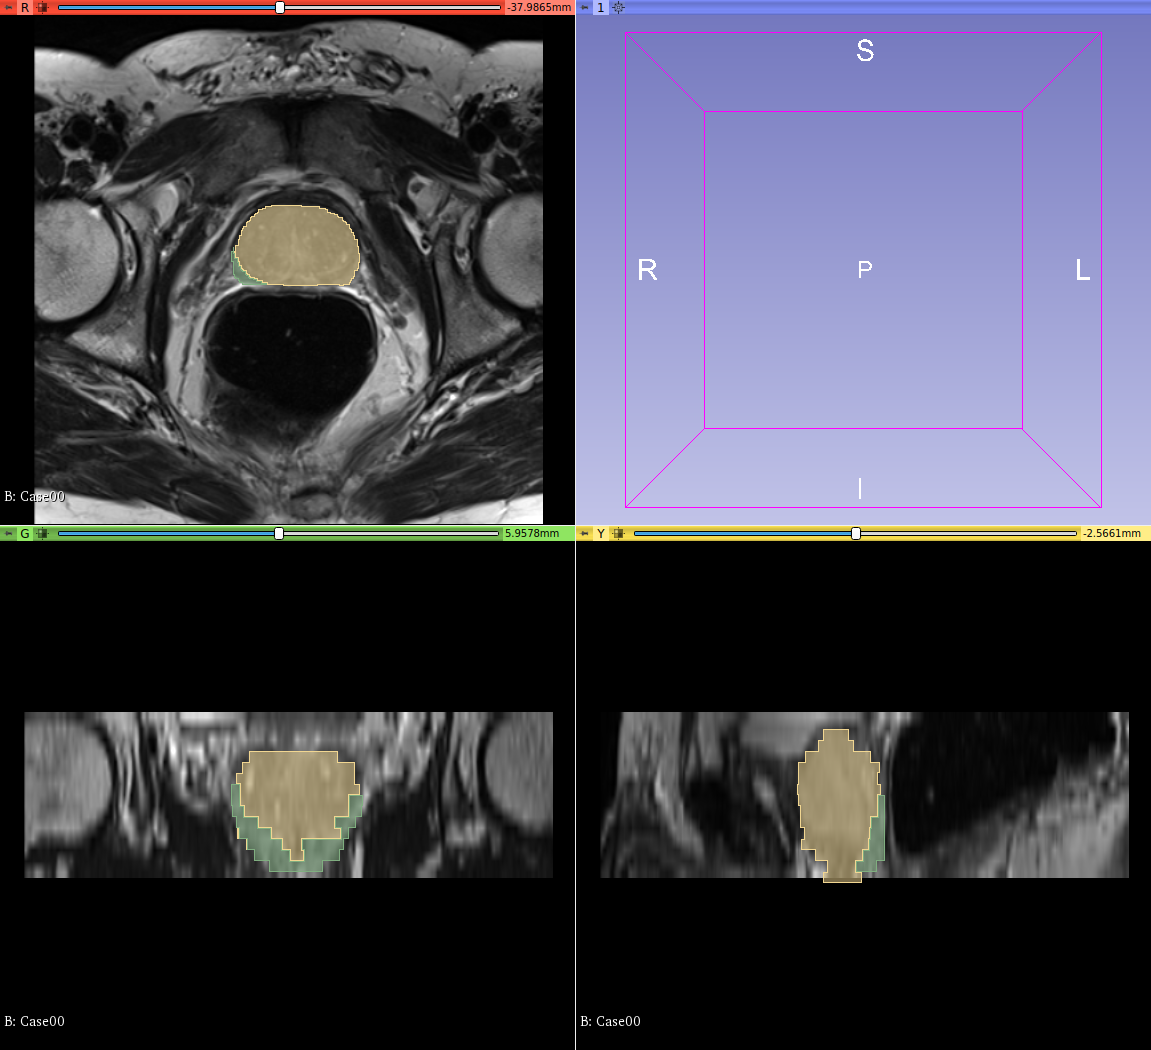

我有前列腺的医学图像,每个图像都有两个解剖标签: label0=背景label1=周边区,Label2=过渡带。

我想把两个标签组合起来,使它们成为一个标签,形成整个前列腺结构,你能帮我做这个吗?

随附的图片更多地证实了我的问题: